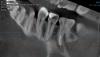

Екатерина У Опубликовано 4 марта, 2011 Автор Поделиться Опубликовано 4 марта, 2011 (изменено) Вот снимок, где видно обнаруженный недавно 4ый корень.2а вопроса:1. В четвертом корне не нашли нерва (может ли быть такое) и дальше половины не можем его пройти. Возможно ли что канал для нерва занимает только половину корня. 2. кто-нибудь видит гранулёму на большом корне на этом снимке? Изменено 4 марта, 2011 пользователем Екатерина У Ссылка на комментарий

АНДРЕЙ ВЯЧЕСЛАВОВИЧ Опубликовано 4 марта, 2011 Поделиться Опубликовано 4 марта, 2011 я думаю это небольшое разряжение , гранулемы или кисты нет. Ссылка на комментарий

АНДРЕЙ ВЯЧЕСЛАВОВИЧ Опубликовано 6 марта, 2011 Поделиться Опубликовано 6 марта, 2011 возможно ,это слепое отверстие.запломбируйте его по всем правилам и не парьтесь.главное соблюдать все принципы эндодонтического лечения. Ссылка на комментарий